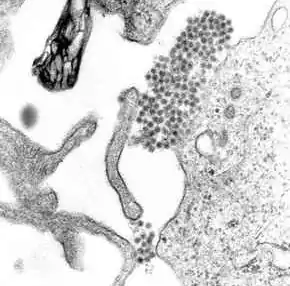

Mosquitoes thrive in the high temperatures and humidity of the Bolivian lowlands and it was that region which saw the highest numbers of infected civilians.[1] There is currently no vaccine for dengue fever.[1] Those infected experience flu-like symptoms such as severe headaches, fevers and joint pain.[1] 1 of 4 people infected with dengue will develop symptoms.[3] There is no specific treatment for dengue, other than managing the symptoms. The best way to address dengue is to disrupt the mosquito's habitat. Mosquitos breed in stagnant water, i.e. open storage containers, discarded tires, and uncollected garbage.[4] The infected are advised by medical experts to drink plenty of fluids and obtain significant rest.[1] Dengue fever sufferers have an approximate 1% chance of progressing to the more severe dengue hemorrhagic fever.[1] 1 of 20 individuals who become ill with dengue will develop severe dengue. Severe dengue can lead to life-threatening condition including shock, internal bleeding, or death.[3] Other symptoms include hypothermia, vomiting, severe abdominal pain and confusion. The global average case-fatality ratio for dengue hemorrhagic fever is 5%.[1]